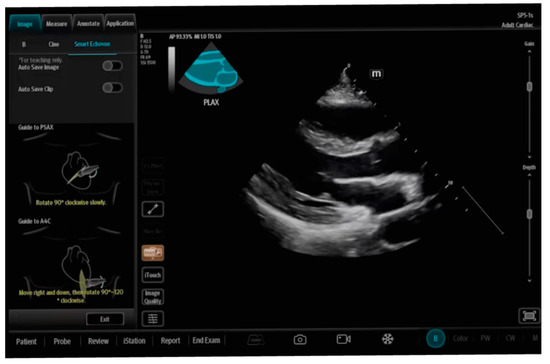

| SmartVTI | Mindray | ||

| SmartEchoVue | Mindray | assessment of views | Whole body |